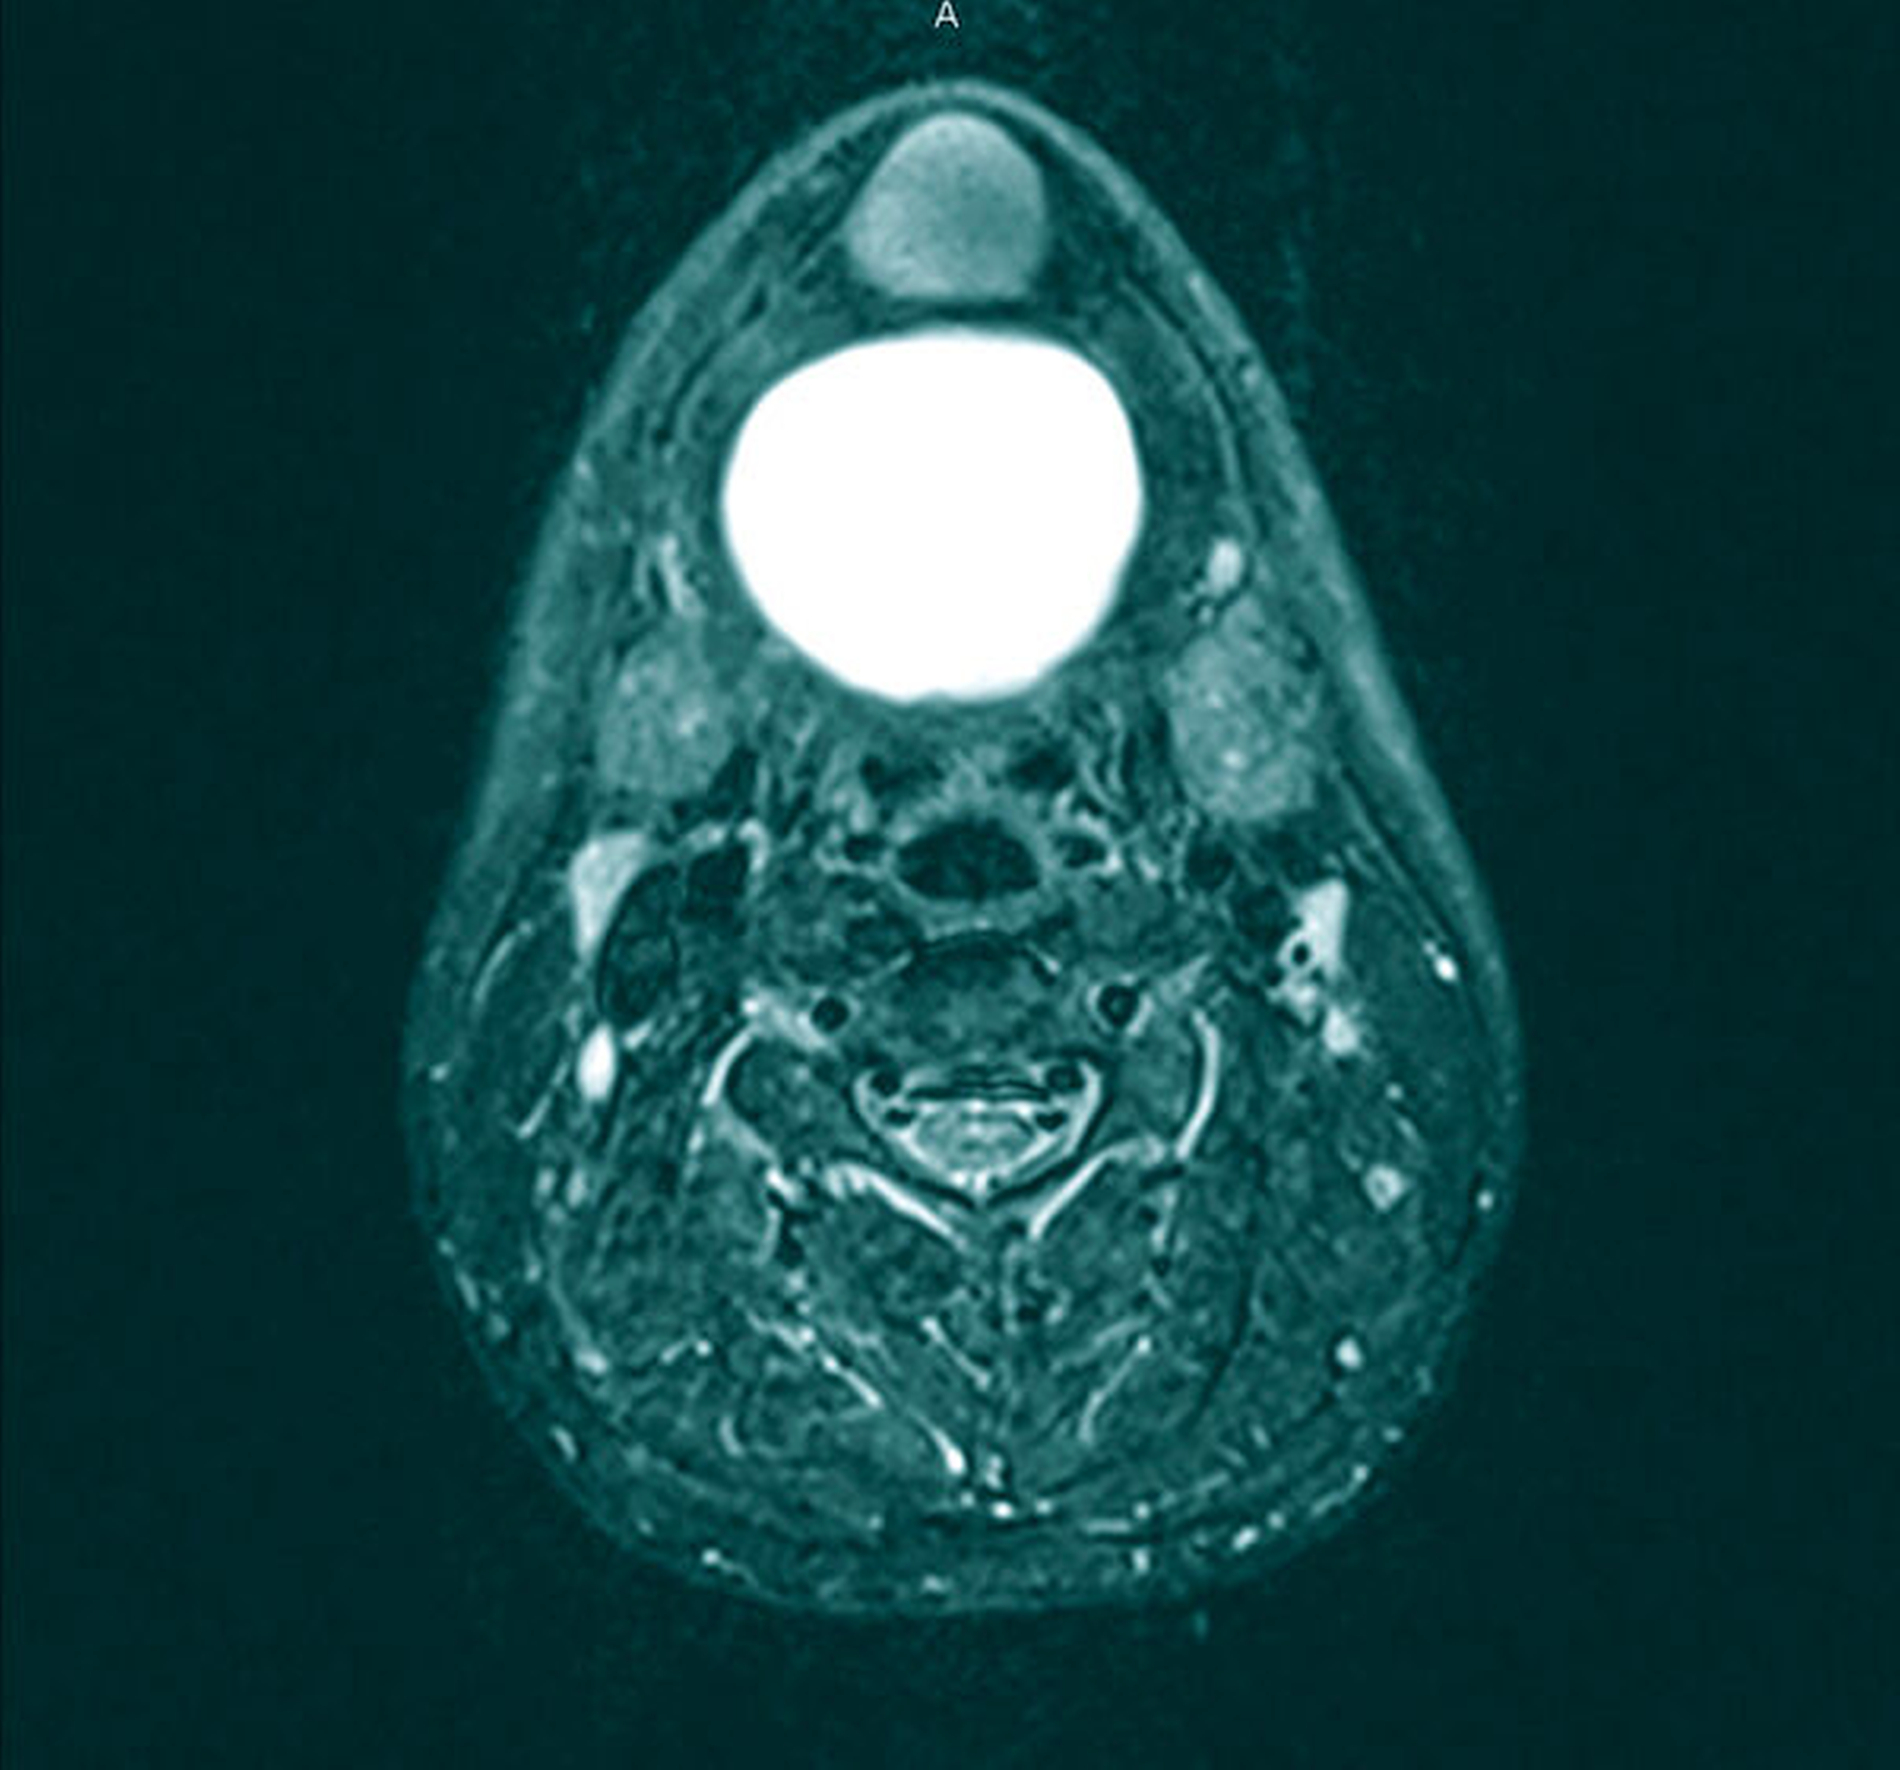

Zur Diagnostik erfolgten eine Sonografie sowie eine Magnetresonanztomografie des Halses. Hierbei kamen zwei voneinander getrennte zystische Raumforderungen submental und im Bereich des Mundbodens zur Darstellung: Die submentale Raumforderung mit einer Größe von maximal 3,5 cm war direkt zwischen der Hautoberfläche und dem M. mylohyoideus, dem Unterkieferknochen angrenzend, lokalisiert. Die zweite Raumforderung mit einer Größe von 6,5 cm erstreckte sich großflächig entlang des gesamten Mundbodens, oberhalb des M. mylohyoideus, mit resultierender Verdrängung der tiefen Zungenmuskulatur und des Zungenkörpers sowie direkter Nachbarschaft zum Ausführungsgang und der Glandula submandibularis beidseitig und ohne Kontakt zum Zungenbein (Abbildungen 3 bis 5).